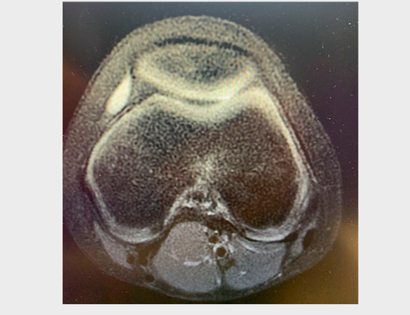

Total scapula replacement! One year follow up! Young teenage patient had an intraarticular resection...

Total scapula replacement! One year follow up! Young teenage patient had an intraarticular resection and free non vascularized fibula for an osteosarcoma in another country. The osteosarcoma recurred along the scapula and the fibula was eroding through the skin.